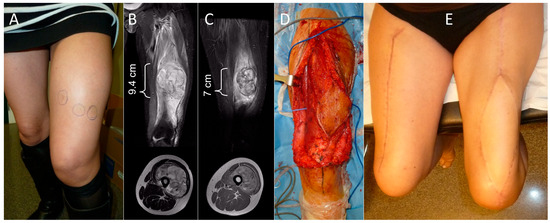

Total Quadriceps Resection in High-Grade Soft-Tissue Sarcomas of the Thigh: Surgical Technique and Long-Term Functional Outcomes in Surviving Patients

by Luis Rafael Ramos Pascua, Paula Casas Ramos, Rubén Álvarez García, Sergio Sánchez Herráez, Cristina Ojeda Thies, Maximiliano Eugenio Negri, Daniel Bustamante Recuenco and Jesús Enrique Vilá Rico

Cancers 2026, 18(1), 37; https://doi.org/10.3390/cancers18010037 - 22 Dec 2025

Background: Reconstruction of the thigh extensor mechanism following wide excision of a soft-tissue sarcoma is difficult. The aim of this study was to describe the outcomes following complete quadriceps resection for large high-grade soft-tissue sarcomas. Methods: Ten patients with AJCC grade IIIB soft-tissue [...] Read more.

Background: Reconstruction of the thigh extensor mechanism following wide excision of a soft-tissue sarcoma is difficult. The aim of this study was to describe the outcomes following complete quadriceps resection for large high-grade soft-tissue sarcomas. Methods: Ten patients with AJCC grade IIIB soft-tissue sarcomas of the anterior thigh were treated with total wide margin quadricectomy, with a mean follow-up of 4 years (range: 51–163 months) in the five surviving patients with conservative surgical procedures. The minimum follow-up period for four of these patients was 8 years. The extensor mechanism was reconstructed with local muscle transfers (eight cases) or a neurotized free flap of the contralateral vastus lateralis (two cases). Results: Four patients died, two due to non-tumor related causes and two due to metastatic disease at 50 months and 43 months. The remaining six were alive and disease-free at the final follow-up. All patients received surgical revision due to wound necrosis. Another patient required an external hemipelvectomy due to early local recurrence of the disease. Functional results of the five patients who remained alive and retained their limb were good or excellent in two cases, acceptable in one, and poor in two, according to their MSTS scores. Average knee flexion was 80° (range: 10–150°). Passive extension was complete in all cases, though no patients achieved it actively. Extensor strength was 2/5 in four patients and 4/5 in the other. Conclusion: Total quadricectomy for high-grade soft-tissue sarcomas of the anterior thigh compartment ensures wide resection margins and local disease control, although local wound complications are common, particularly in older patients. Resection appears to be technically easier if performed distally to proximally in the thigh. Local muscle transfers are more suited for low-demand patients, while neurotized free muscle flaps are mainly an option for young, motivated patients. Full article

Show Figures

Figure 1